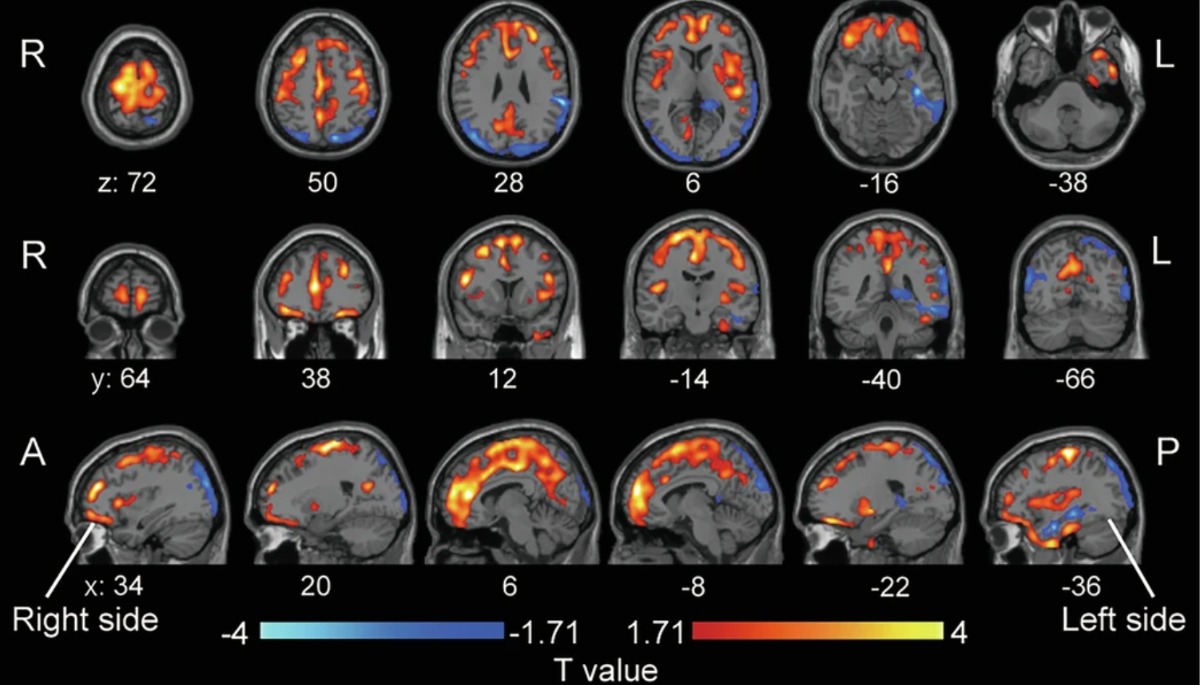

đź§  Brain Scans Reveal How Ketamine Works

New research suggests ketamine may help treat depression by improving how brain cells communicate. In the study, researchers found that people with more severe depression had abnormal activity in AMPA receptors, which are involved in neuroplasticity—the brain’s ability to heal and form new connections.

After a series of ketamine infusions, these patterns shifted in ways linked to improved depressive symptoms, suggesting ketamine may work in part by restoring healthier brain signaling, helping the brain recover, and promoting neuroplasticity.

This brain image highlights regions where the baseline density of AMPA receptors predicted how well patients responded to ketamine treatment. Areas shown in color represent brain regions where receptor activity before treatment was linked to greater improvement in depression symptoms after ketamine therapy, suggesting that AMPA receptors may play an important role in ketamine’s antidepressant effects.